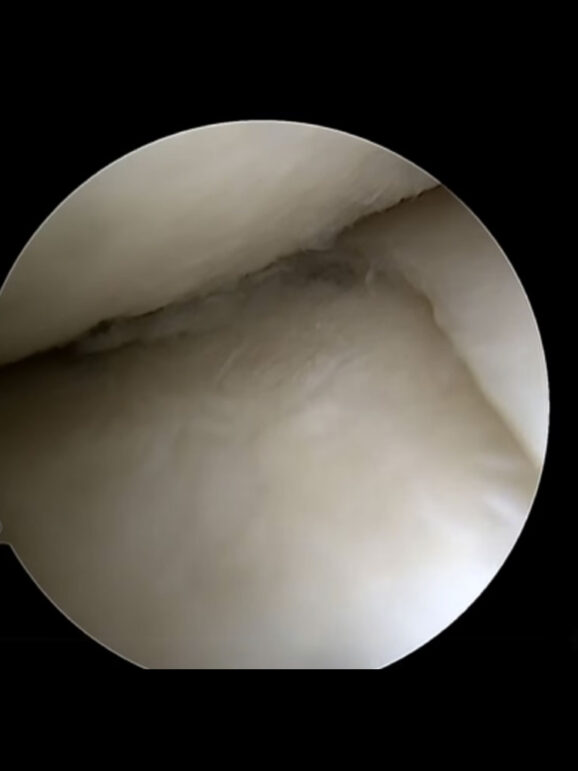

CASE STUDIES

Δείτε μερικές Επεμβάσεις μας